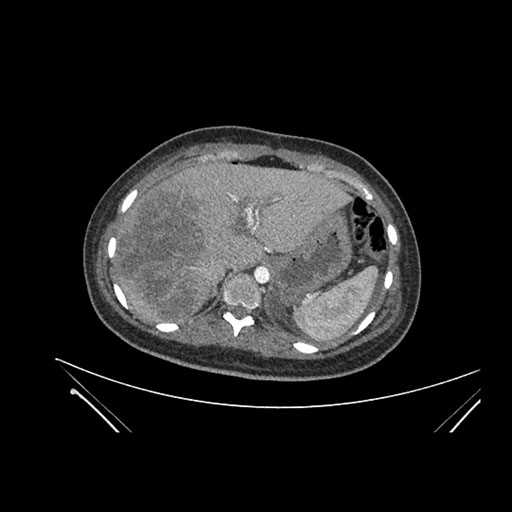

Imaging Analysis

Look through the patient's CT scan to identify any areas of concern for the necessary procedure.

Axial Venous

Based on initial findings, which issue(s) would you be most concerned about?